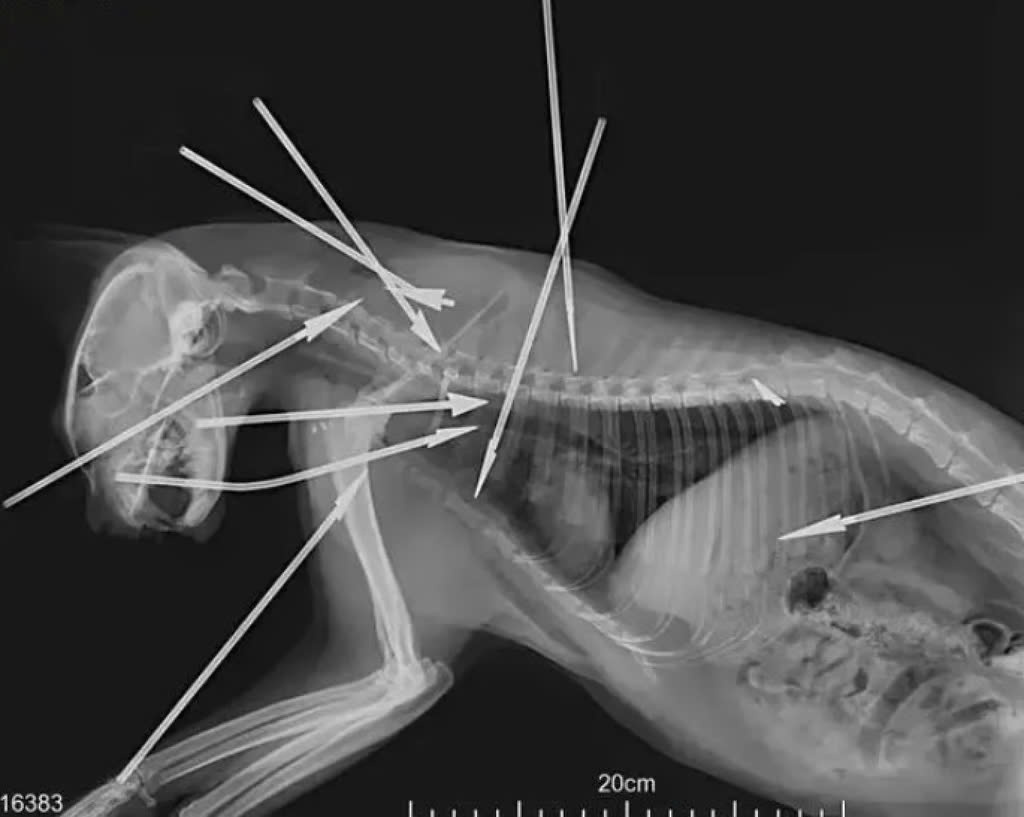

Đài truyền hình Chiết Giang đưa tin vào ngày 13/8, các tình nguyện viên đã tìm thấy một con mèo hoang tại Qinqin Home (khu dân cư ở Hàng Châu, tỉnh Chiết Giang) với 10 phi tiêu thép găm vào đầu, ngực và lưng.

Đầu và thân con mèo bị găm bởi 10 phi tiêu thép, dẫn đến cái chết của nó.